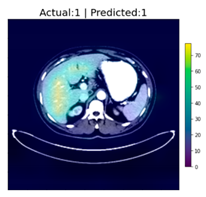

| Image Number | Overlaid Image | Deep Lesion Label | CNN Result | Clinical Radiologist’s Diagnosis | Grad-CAM Helpfulness |

|---|---|---|---|---|---|

| 1 | ![]() | Has Tumor | Has Tumor | Has Tumor | Some |

| 2 | ![]() | Has Tumor | Has Tumor | Has Tumor | Yes |

| 3 | ![]() | Has Tumor | Has Tumor | Has Tumor | Yes |

| 4 | ![]() | Has Tumor | Has Tumor | Has Tumor | Yes |

| 5 | ![]() | Has Tumor | Has Tumor | Has Tumor | Yes |

| 6 | ![]() | No Tumor | Has Tumor | Has Tumor | Yes |

| 7 | ![]() | Has Tumor | Has Tumor | Has Tumor | Yes |

| 8 | ![]() | Has Tumor | Has Tumor | Has Tumor | Yes |

| 9 | ![]() | Has Tumor | Has Tumor | Has Tumor | Some |

| 10 | ![]() | Has Tumor | Has Tumor | Has Tumor | Yes |

| 11 | ![]() | Has Tumor | Has Tumor | No Tumor (Cyst) | Some |

| 12 | ![]() | Has Tumor | Has Tumor | Has Tumor | Yes |

| 13 | ![]() | Has Tumor | Has Tumor | No Tumor | Yes |

| 14 | ![]() | Has Tumor | Has Tumor | No Tumor (Inflammation of the Biliary Tract) | Some |

| 15 | ![]() | No Tumor | Has Tumor | No Tumor (Cyst) | Some |

| 16 | ![]() | Has Tumor | Has Tumor | Has Tumor | Yes |